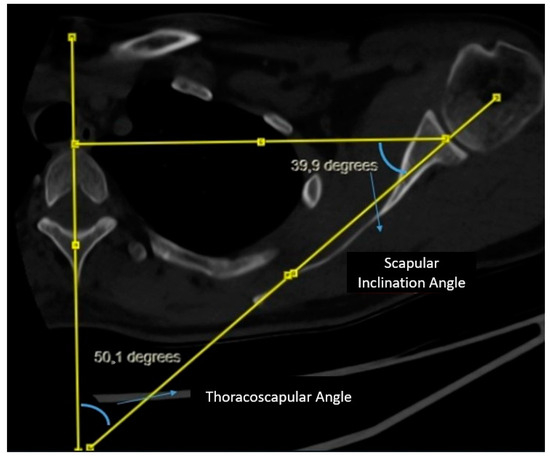

Measurement of Scapular Inclination Angle and Thoracoscapular Angle: A vertical line is drawn from the midline of the corpus and spinous process of the thoracic vertebra at the level of the spine of the scapula. Subsequently, a second line connecting the center of the glenoid to the spine of the scapula is drawn, intersecting the line through the midline of the thoracic vertebra. A triangle is formed by drawing a line from the center of the glenoid perpendicular to the vertical line on the vertebra. The angle between the line connecting the center of the glenoid to the spine of the scapula and the line drawn perpendicular from the center of the glenoid to the vertical line on the vertebra is evaluated as the scapular inclination angle. The angle between the line connecting the center of the glenoid to the spine of the scapula and the vertical line on the midline of the vertebra is evaluated as the thoracoscapular angle. It is noteworthy that the scapular inclination angle and thoracoscapular angle together complement each other to form a total of 90 degrees (Figure 2).

Figure 2. Measurement of scapular inclination and thoracoscapular angle.